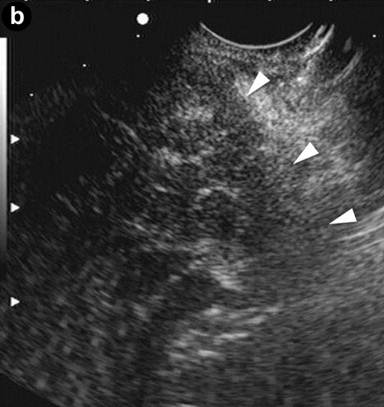

A 36-year-old man with jaundice and mild abdominal pain. Computed tomography (CT) showed dilated intra- and extra-hepatic bile ducts with diffuse pancreatic swelling. EUS linear scanning (Image 2a) showed an enlarged pancreatic head with an irregular hypoechoic lesion, loss of interface (arrowhead) with the superior mesenteric vein (smv), and a normal main pancreatic duct (arrow). The remaining pancreas (Image 2b) was also diffusely enlarged with hypoechoic echotexture and hyperechoic septa. The patient responded to steroid therapy.